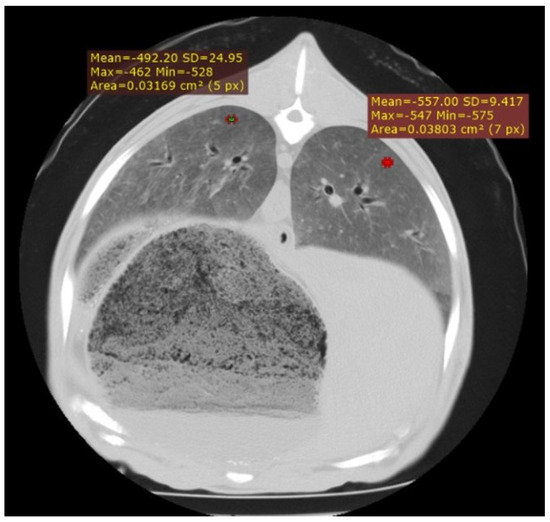

Use of Computed Tomography in the Clinical Diagnosis of Lower Respiratory Tract Diseases in Sheep

Lower airway diseases are a major health concern in sheep, often presenting with overlapping clinical signs that hinder accurate diagnosis. This study evaluated the diagnostic value of computed tomography (CT) in 58 adult sheep examined in northeastern Spain between 2017 and 2024. All animals underwent full clinical examination, CT under general anaesthesia, and post-mortem investigation. CT identified 82 pulmonary lesions, including interstitial pneumonia, respiratory complex, gangrenous pneumonia, caseous lymphadenitis, parasitic pneumonia, pulmonary adenocarcinoma, and pulmonary hydatidosis. Tissue density measurements provided additional information regarding disease stage and severity. The level of agreement between CT findings and definitive diagnoses consistently exceeded that of clinical evaluation, reaching almost perfect concordance for several conditions. Moreover, CT revealed concomitant respiratory pathologies within the same animal, many of which were not detected by conventional diagnostic methods. Although thorough individual clinical examination remains essential for the correct interpretation of imaging findings and the accurate diagnosis of respiratory disorders in the field, these results demonstrate that CT provides superior diagnostic accuracy compared with standard approaches and yields valuable insights for both clinical practice and research. Despite its practical limitations, CT could represent a major advance in improving health, welfare, and productivity in sheep farming. Full article